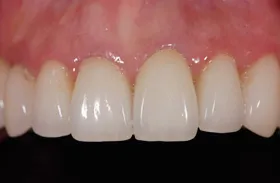

前歯欠損の為来院されたケース

■治療前

■治療後

治療のポイント

- 骨幅が狭い状態です。

- インプラントを埋めると同時に、骨を作る処置をさせて頂きました。

| 主訴 | 上顎の抜歯した箇所の機能障害・審美障害 |

|---|---|

| 治療方法 | 上顎の欠損部位に1本のインプラントを埋入し、同時に外科的治療で骨造成を行った |

| 治療期間 | 約1年 |

| 通院回数等 | 10回 |

| 費用 | 550,000円(税込) |

| リスク・副作用 | 外科的に骨を作る為、治療後に腫れることがある |